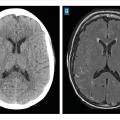

Le scanner doit être réalisé en urgence. Il montre une hyperdensité des espaces sous-arachnoïdiens, évalue la sévérité par l’échelle de Fisher et recherche les complications précoces (fig. 1 et tableau 1).

Si l’IRM est accessible et que l’état du patient est compatible, les séquences FLAIR, T2* ou imagerie pondérée en susceptibilité magnétique (SWI) peuvent remplacer le scanner cérébral sans injection (fig. 2), avec une sensibilité plus élevée pour le diagnostic d’hémorragie méningée.